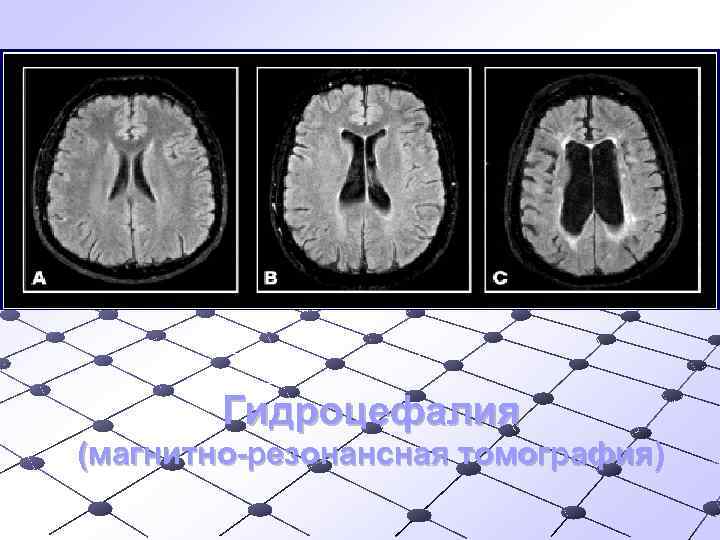

Гидроцефалия (магнитно-резонансная томография)